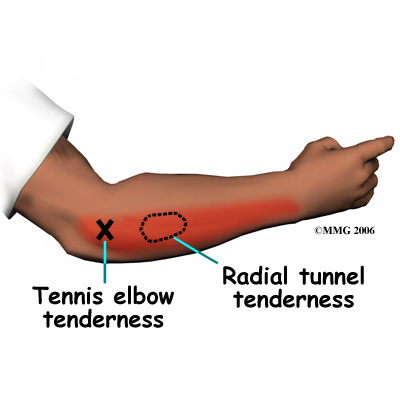

The symptoms of radial tunnel syndrome are tenderness and pain on the outside of the elbow. The symptoms of radial tunnel syndrome are very similar to the symptoms of tennis elbow. As in tennis elbow, pain from radial tunnel syndrome often starts near the lateral epicondyle. (The lateral epicondyle is a bony point on the outside of your elbow joint.) The pain gets worse when you bend your wrist backward, turn your palm upward, or hold something with a stiff wrist or straightened elbow.

One difference between radial tunnel syndrome and tennis elbow is the exact location of the pain. In tennis elbow, the pain starts where the tendon attaches to the lateral epicondyle. In radial tunnel syndrome, the pain is centered about two inches further down the arm, over the spot where the radial nerve goes under the supinator muscle. Radial tunnel syndrome may also cause a more achy type of pain or fatigue in the muscles of the forearm. Nerve pressure inside the radial tunnel leads to weakness in the muscles on the back of the forearm and wrist, making it difficult to steady the wrist when grasping and lifting. It can even lead to wrist drop, meaning the back of the hand can't be cocked up. Skin sensation is not changed because the sensory portion of the radial nerve branches off above the elbow and does not enter the radial tunnel.